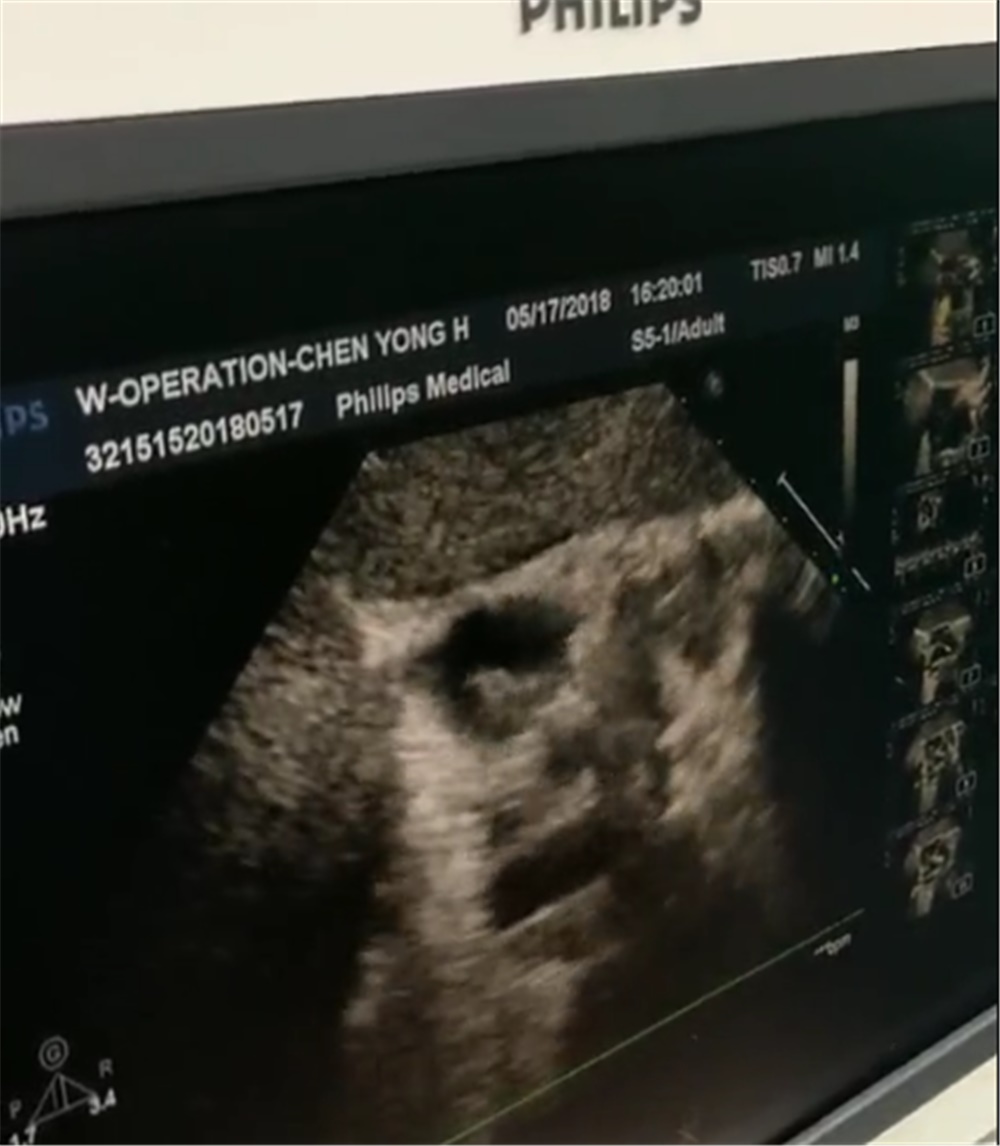

治疗方案连连被否,医生们接下来会给出怎样的“放伞”方式呢?曹建军说,“我思考了很长时间,经过反复讨论,最终选择还是给这个小孩做经胸骨旁,经胸壁的小切口B超引导下的房间隔缺损的封堵方式。”

那么,和前两种方案相比,这种方式有着怎样的特点和优势呢?貌似做了一个两公分的切口,貌似它比经大腿穿刺的切口似乎是要大一些,但是它有明显的优势。首先,手术在B超的引导下进行,完全地避免了大剂量X线的照射,对于小孩的保护是有益的。第二,采用这种方式,可以避免长距离的在血管内操作,也就避免了血管内皮损伤,造成血管栓塞、狭窄等严重后果的可能性。“它比介入的方式更直接,因为我的鞘管到房间隔缺损的距离更短,我是在右心房直接做一个荷包穿刺,那么它到房间隔缺损也就是心房壁到房间隔缺损就是几公分的距离。” 曹建军介绍。

虽然确定了治疗方案,但医生们的压力却并未减轻。因为这种方式刚刚兴起,在行业内也只有零星的应用,没有过多的经验可资借鉴,这又成了摆在医生们面前的一道难题。为了确保万无一失,术前医生反复把这个小孩带到B超下,从多个体位反复去看,去找这个房缺,去模拟我们手术的途径,做了多套预案之后才实施手术。